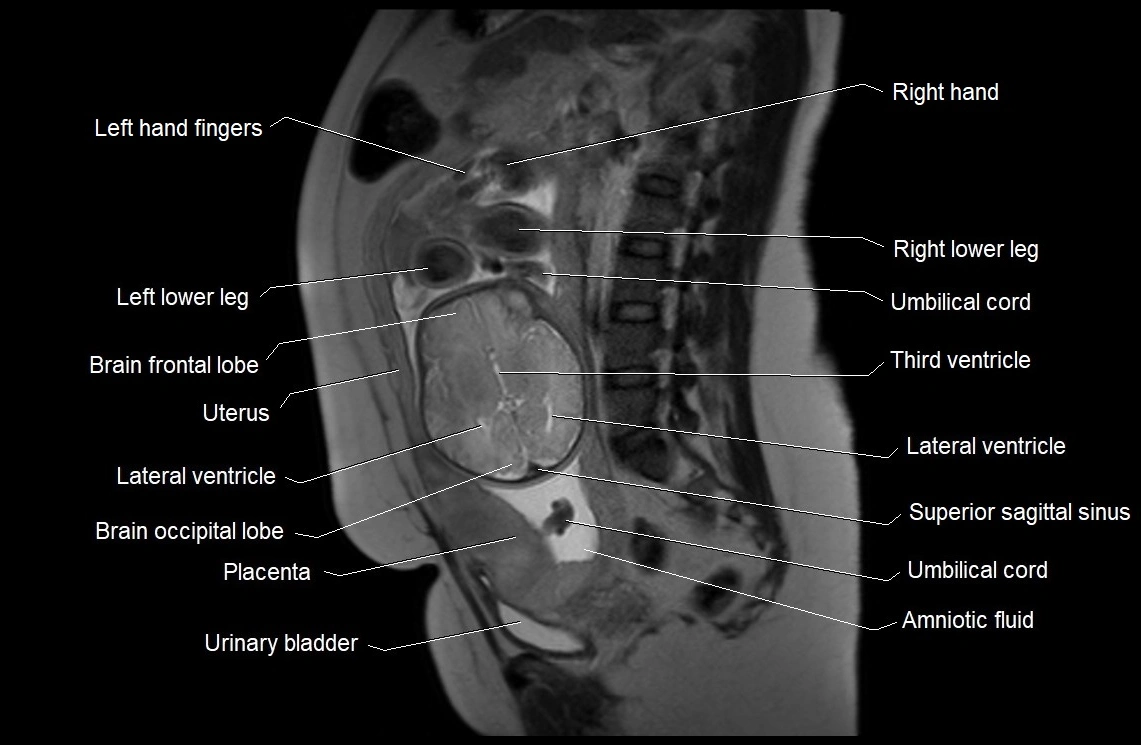

MRI Appearance

T2 HASTE (T2 GRE):

• Amniotic fluid shows very bright hyperintense signal

• Provides natural contrast against fetus and placenta

• Small particles (vernix) may appear as scattered hypointense foci within bright fluid

T1 GRE:

• Amniotic fluid shows low signal intensity (dark)

• Hemorrhage, infection, or proteinaceous content may cause focal or diffuse high signal intensity